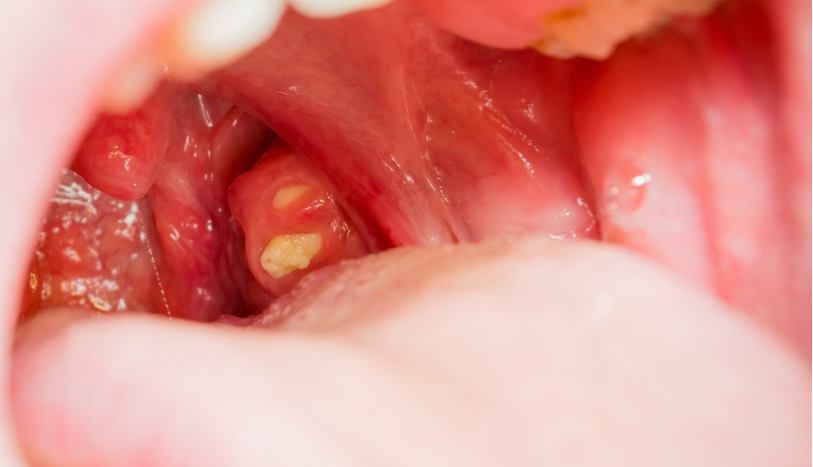

편도결석이란 편도 표면에 존재하는 작은 구멍(편도음과)사이에 음식물 찌꺼기나 세균이 결합된 밥알과 같은 알갱이가 생성된 것을 말합니다.

약 5밀리미터 정도의 크기에서 1.5센티미터 정도의 거대 결석도 볼 수 있습니다. 기침이나 가래를 뱉는 등의 행동에 의해 자연스럽게 배출되는 경우도 있습니다만, 처치 없이는 제거되지 않는 타입도 있습니다.

• 타액이나 음식 등을 삼킬 때 뭔가 걸리는 것 같은 이물감이 느껴집니다.· 목이 간질간질한 감각이 발생합니다.·입 안을 플래시로 비추거나 관찰하면, 노란색 알갱이가 보입니다.· 구강 청결을 유도하는데도 생선의 비린내와 유사한 구취가 발생합니다.· 메스꺼움이나 기침, 가래를 뱉는 등의 행동을 할 때 알갱이가 튀어나옵니다.• 별 병이 없어도 헛기침이 나와요.·음식을 하지 않아도, 무엇인가가 목구멍 깊숙이 내려가는 듯한 느낌이 듭니다.